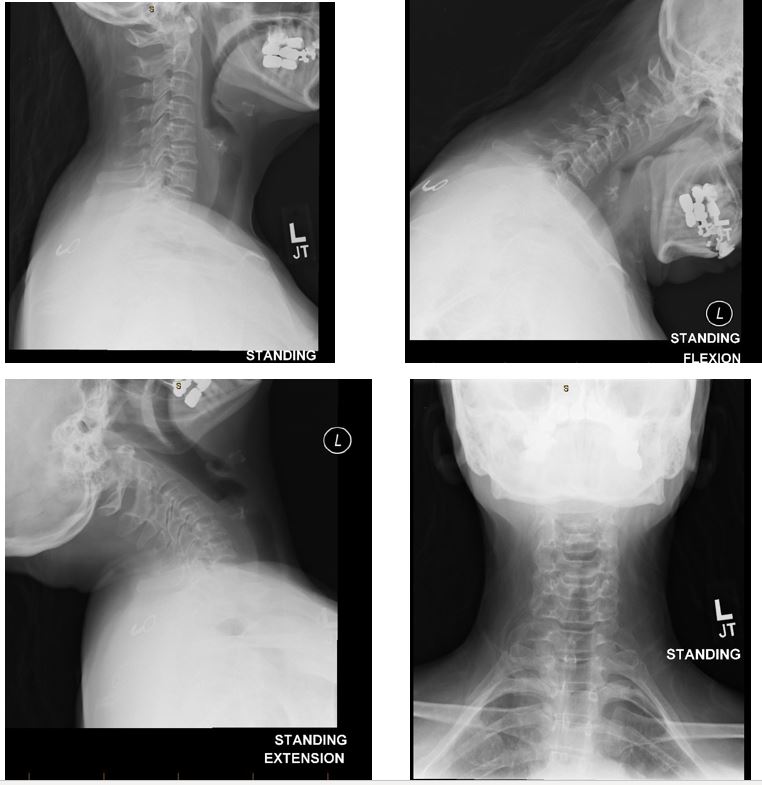

Over the next four weeks, the patient returned to the neurosurgeon four times on a weekly basis. Each week he ordered a different study.   She received flexion/extension x-rays, then a CT scan, and finally a nerve conduction study.

CT Scan C7T1

Her flexion extension x-ray showed a 2 mm anterior slip at C7/T1 which he felt was not severe enough to warrant surgery.   NCV testing concluded a right radiculopathy and left peripheral neuropathy.  The surgeon concluded that it was a right C6/7 radiculopathy and a left ulnar peripheral neuropathy.